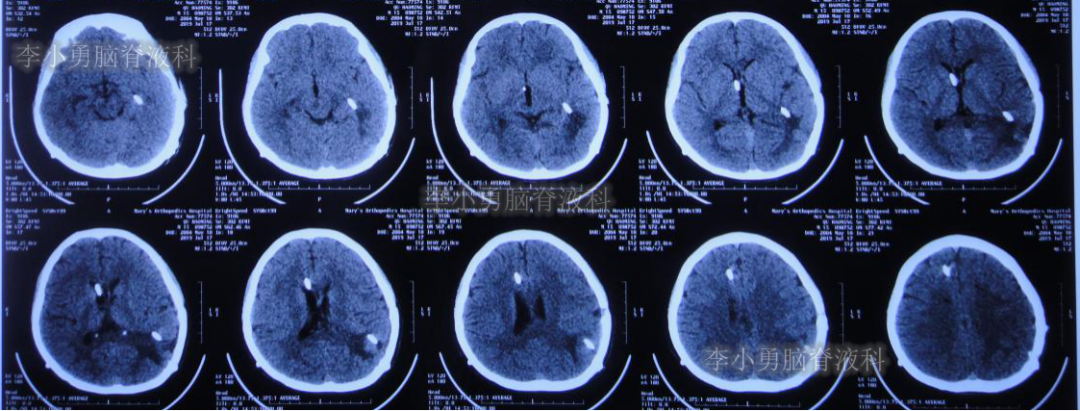

2019年3月26日患者突发头痛及呕吐,随后出现晕厥。急救车送至河南省周口市某医院。行头颅CT(图-1):脑室内出血,次日急诊给予行双侧脑室外引流术(图-2)(第一次的脑室外引流术)。

图-1:2019年3月26日头颅CT:脑室内出血

图-2:2019年3月27日头颅CT:双侧脑室外引流术后